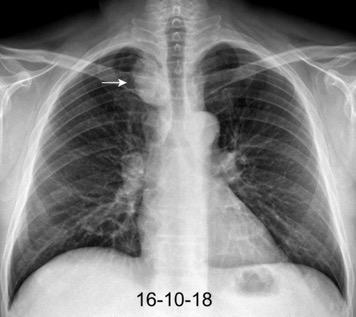

De los pacientes con Tumor de Pancoast

1,7% tienen una radiografía de tórax normal

Fletcher F et al. The normal chest radiograph in bronchial carcinoma. Br Med J. 1976

Hallazgos en TC de invasión local Fiabilidad diagnóstica: 62,7-72,3%.

Valor predictivo positivo: 41,1%-56,4%.

La predicción basada en TC es un falso positivo en casi 50% de los casos